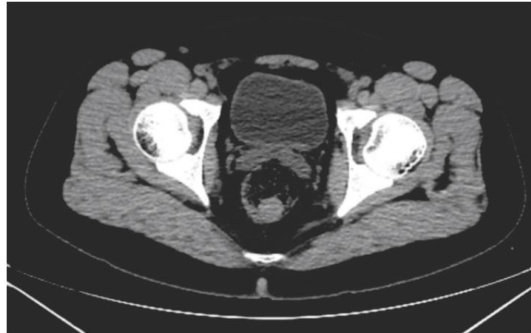

摘要:肺动脉取栓是治疗急性肺栓塞(PE)的重要方法,其成功实施依赖于多学科团队的紧密协作。本文通过1例急性PE患者的诊疗过程,探讨肺动脉取栓的适应证、手术策略及多学科诊疗(MDT)的关键环节。该患者因喘憋就诊,经影像学确诊为肺栓塞,危险分层为中高危,在呼吸内科、心内科、心外科、影像科、超声科等多学科协作下,成功实施了经皮机械血栓清除术。术后患者血流再通、症状显著缓解,未发生严重并发症。该文为临床医生提供了肺动脉取栓MDT的参考框架,优化了肺栓塞患者的救治流程,为肺栓塞取栓治疗的病例选择和诊疗策略提供参考。